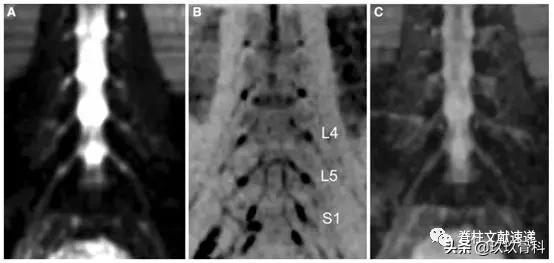

图注:健康志愿者腰椎神经根冠状扩散加权图像(DWI)。L4、L5和S1表示腰4、5骶1神经根。C图是基于DWI计算得到的ADC图。

图注:背根神经节的角度(A),背根神经节的长度和宽度(B)的大小,以及健康志愿者近端/远端神经根平均ADC值 (C)。L4-L5背根神经节的角度40°,急剧下降到S1的25°。神经节的长度从L4增加到S1,宽度在L5处逐渐增加到最大值,在S1处逐渐减小。L4-S1神经根ADC值高于远端神经。